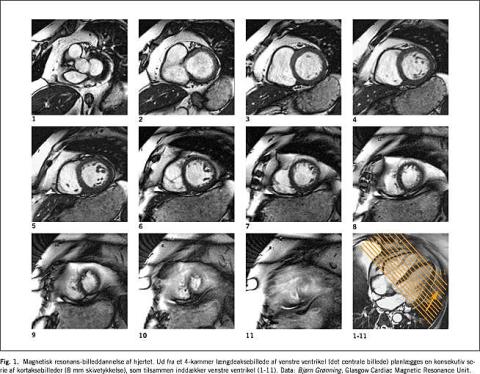

Den vigtigste CMR-metode til vurdering af venstre ventrikel bygger på inddækning af ventriklen ved hjælp af en stak billedskiver placeret perpendikulært til ventriklens længdeakse (tværsnitsskiver), hvorved ventriklen beskrives i tre dimensioner uden behov for geometriske antagelser om ventriklens form (Figur 1 ) [5]. Hver af disse skiver (6-8 mm tykke) optages ekg-styret ved hjælp af en cinematografisk (CINE) pulssekvens, som optager en tidsserie af billeder af hver skive. Første billede optages svarende til R-takken i ekg'et (slutdiastole), andet billede hurtigt herefter (20-40 ms) og så fremdeles til hele R-R-intervallet er inddækket (15-20 billeder). Oftest optages hver skive for sig, mens patienten holder vejret (3-10 s) for at minimere respiratoriske artefakter. Den totale venstre ventrikel-skanningstid ligger på under 10 min ved brug af moderne skannere.

På hver af de optagne skiver indtegnes endo- og epikardiegrænserne manuelt eller semiautomatisk, hvorved man opnår reproducerbare mål for ventriklens slutdiastoliske og slutsystoliske volumina, myokardiemasse og LVEF.